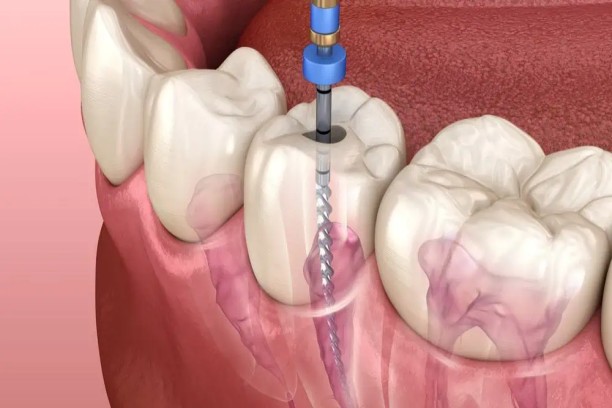

Pulp Therapy

Treatment to save infected baby teeth and relieve pain.